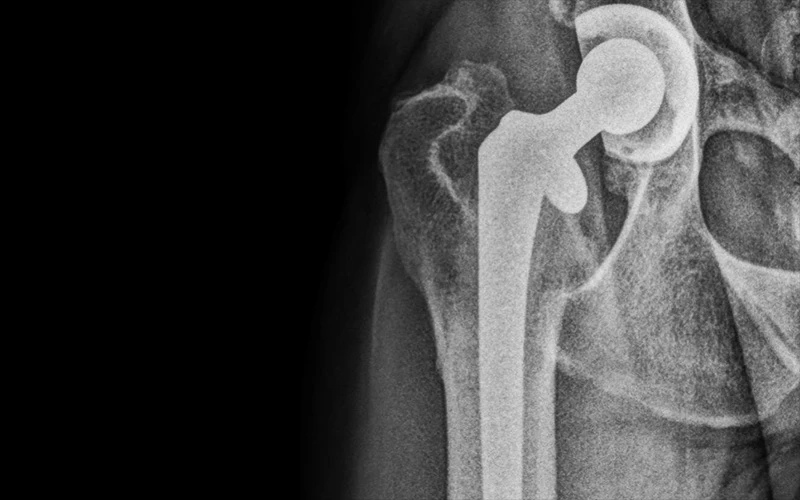

Hip Replacement at 3D Sports Medicine and Orthopaedic Center

From www.hopkinsmedicine.org